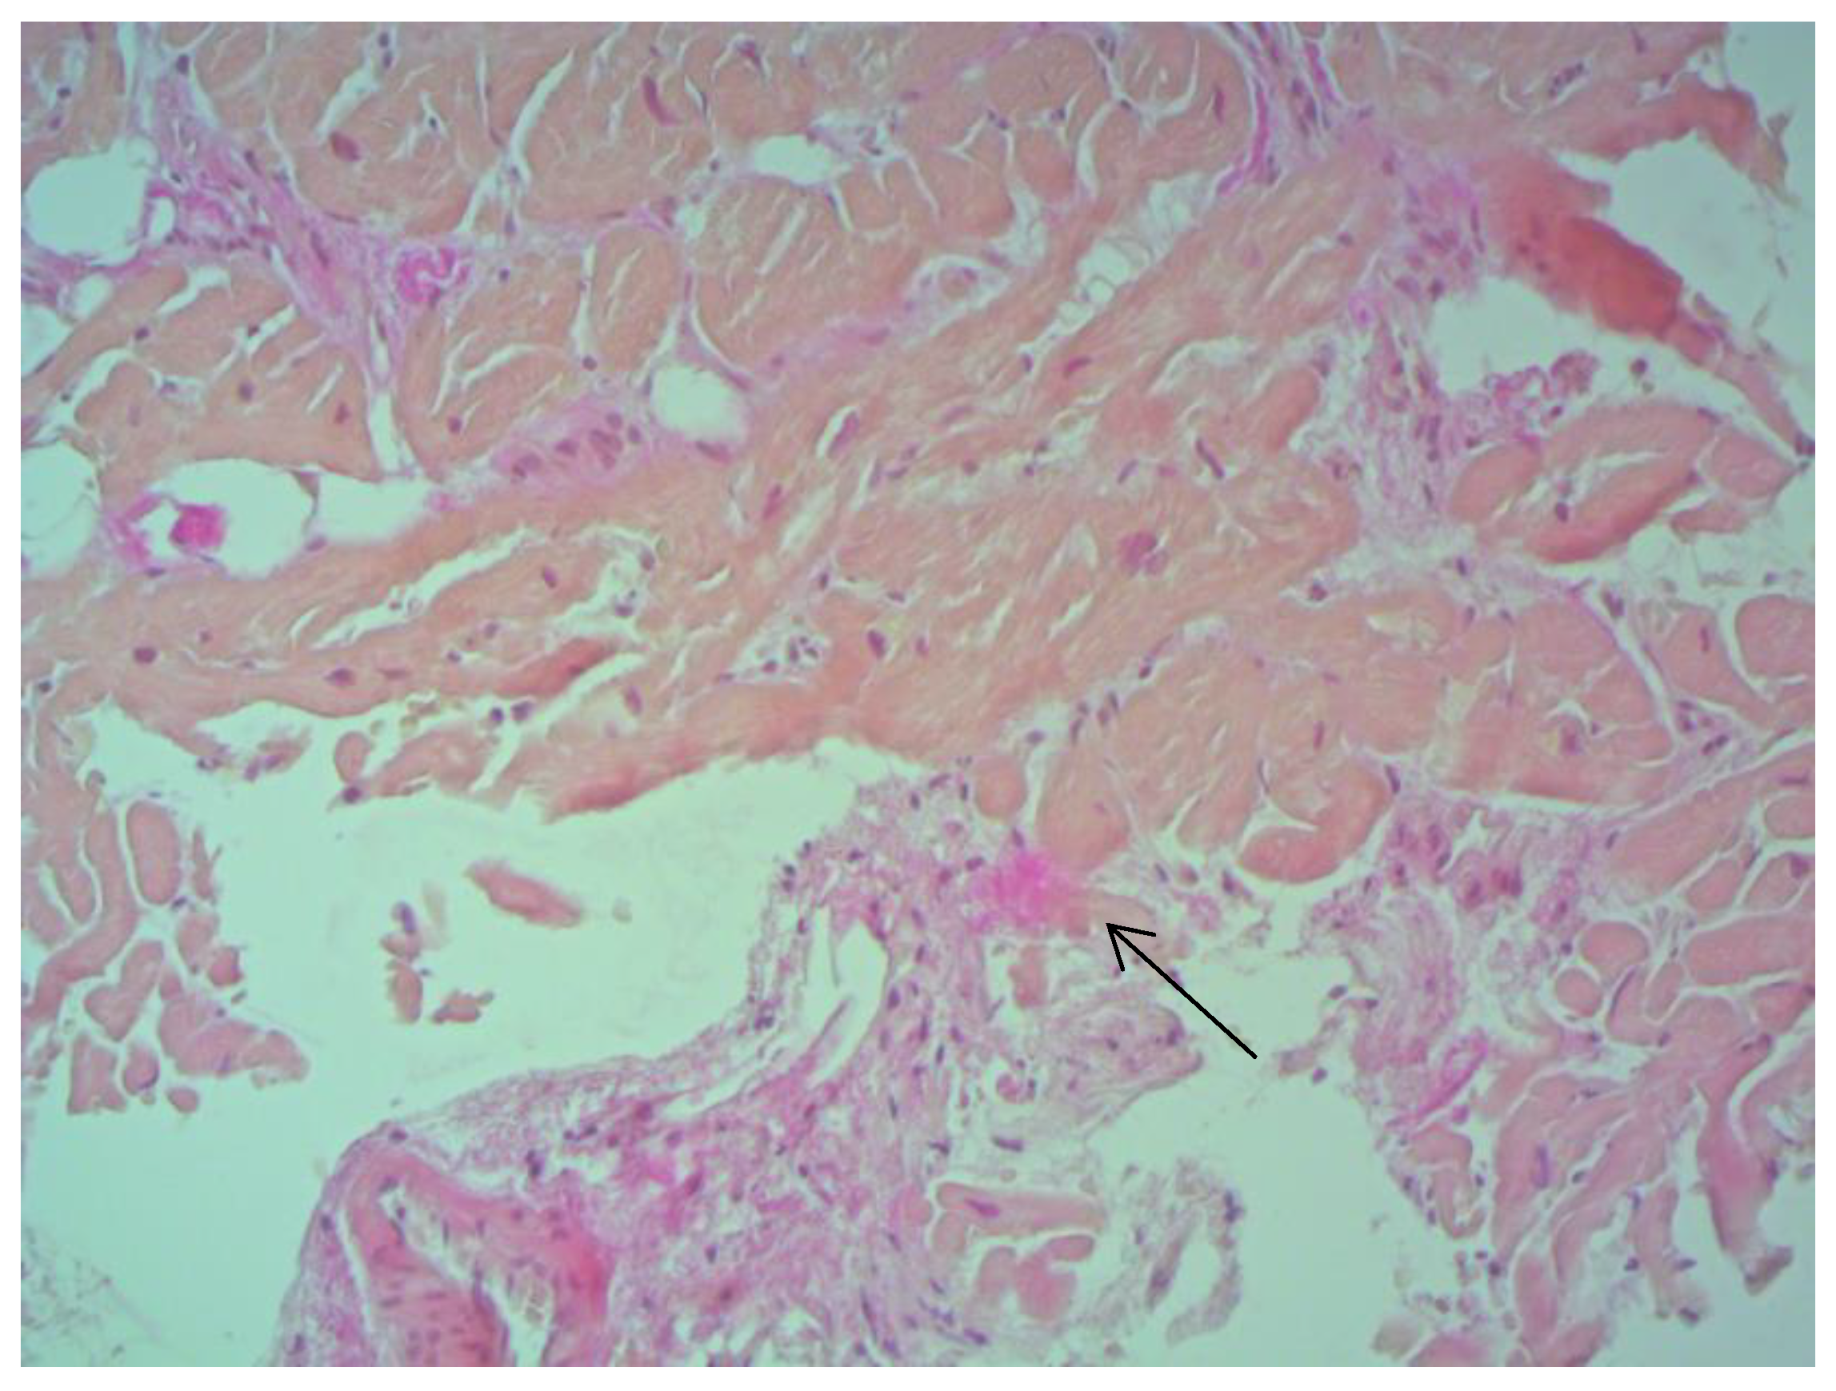

According to EMB results, no histological changes in the myocardium of the right ventricle (RV) were found in nine patients (13.4%). Fibrotic changes in the myocardium were detected in 26 cases (38.8%) including in predominantly perivascular fibrosis in 11 patients (42.3%), small focal fibrosis in eight patients (30.8%), and perimuscular fibrosis in seven patients (26.9%) (Figure 1, Figure 2 and Figure 3).

Figure 3. Fibrosis in IAS ×200, staining according to Van Gieson. The arrows indicate the foci of connective tissue proliferation.